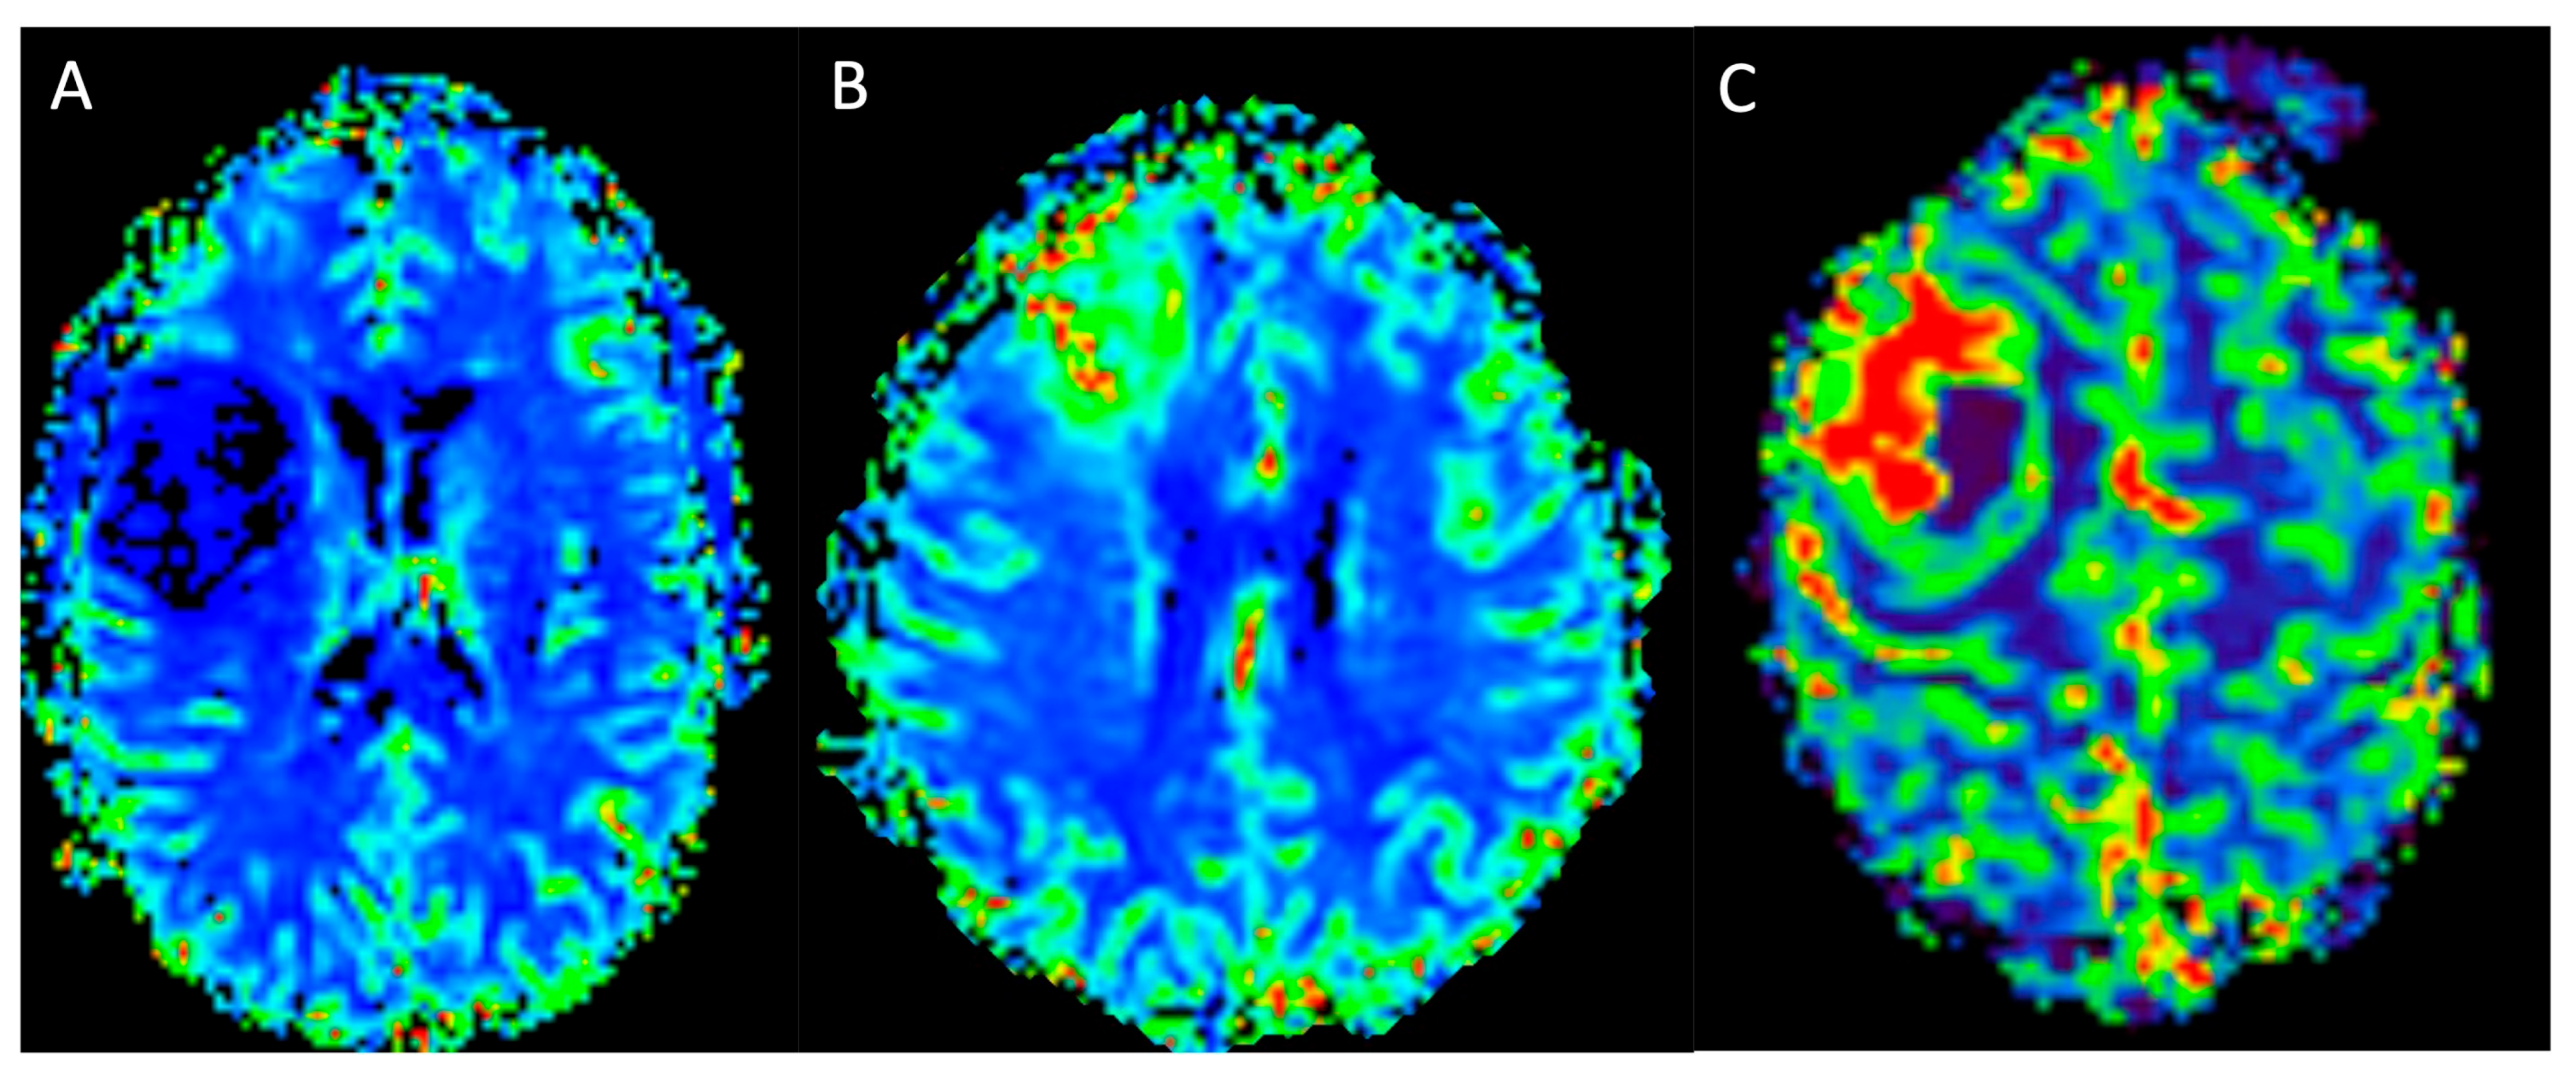

2.2.2. Perfusion-Weighted Imaging

Dynamic Susceptibility Contrast

Dynamic Contrast Enhancement

Arterial Spin Labelling